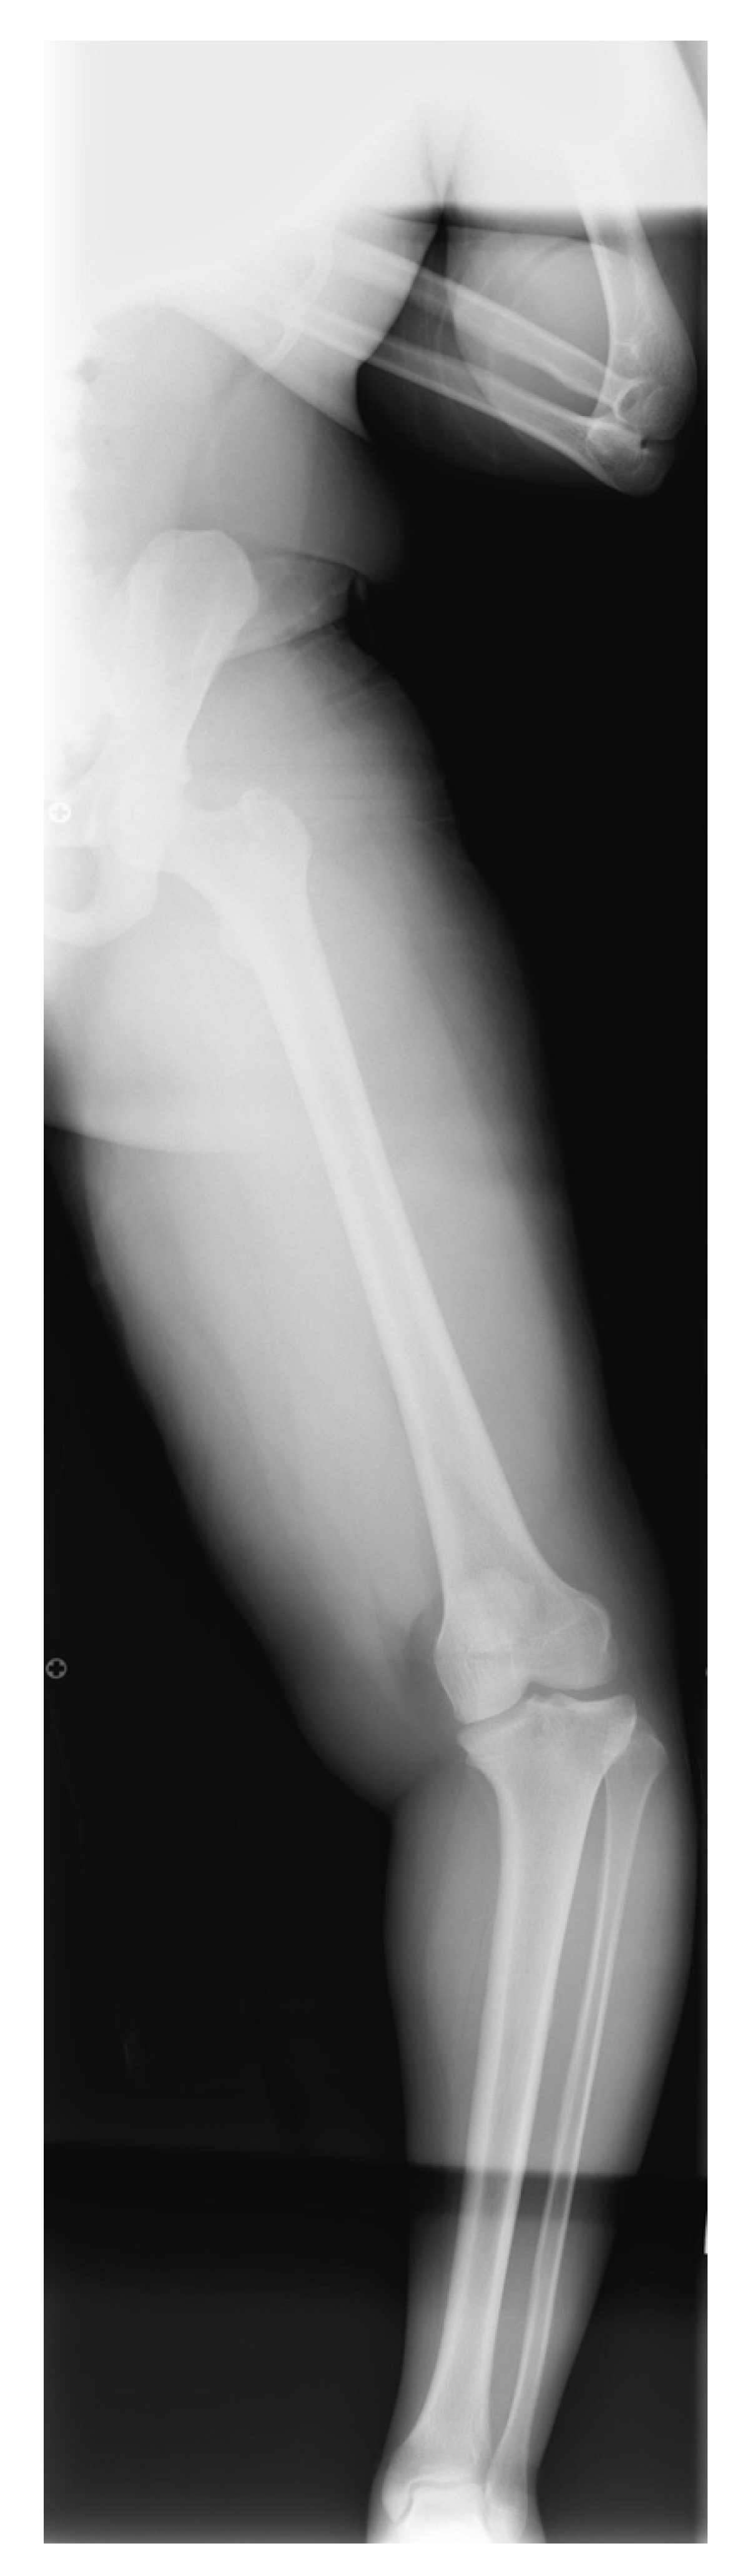

17. Gradual Correction with External Fixation